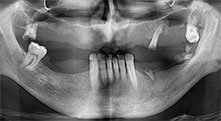

¿Podría describirnos brevemente cómo procede, por ejemplo, a la hora de mover injertos óseos destinados a trasplantes?

Bratu: Preferimos realizar las osteotomías en la línea oblicua externa de la cara posterior del maxilar inferior, y no en la región situada entre los orificios. Tras realizar una incisión en los tejidos blandos, utilizamos las nuevas sierras para definir el contorno de la osteotomía. De este modo, conseguimos una preparación completa en prácticamente el 80 por ciento de los casos. Por otro lado, en algunas ocasiones también utilizamos otros insertos piezoquirúrgicos, así como un cincel para mover el injerto. Para nosotros, esta es una técnica de intervención muy eficaz.

Bratu: Nos gusta utilizar la técnica de sándwich para realizar aumentos en la cara lateral del maxilar inferior. En este procedimiento, se utiliza la sierra piezoquirúrgica para preparar una tapa ósea, mientras que el fragmento crestal se fija con microtornillos. Entre medias, colocamos una combinación de hueso autólogo y material óseo adicional xenógeno. Y con ello obtenemos un rendimiento muy fiable. Asimismo, en los ranurados de la cresta alveolar del maxilar inferior, nunca se puede prescindir de cortes verticales suficientemente dimensionados, pues, de lo contrario, los huesos pueden fracturarse fácilmente.